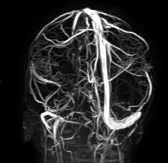

Il follow-up di neuroimaging a 12 mesi ha mostrato una completa risoluzione della trombosi (Figura 4), pertanto ha sospeso la terapia con anticoagulante ed è tornata a mangiare spinaci!